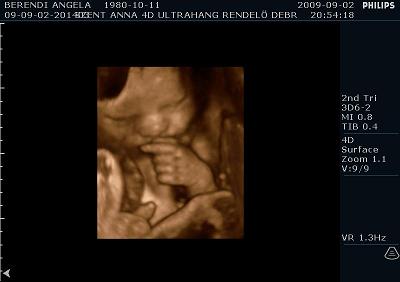

Ma voltunk UH-on. És a méretei alapján még mindig egy héttel idősebbnek nézik, de súlya tök normális 2350 gramm. Szóval azt mondják nem lesz akkora mint a kis Levi manó volt. Ennek azért örülök mert nagyobb az esély hogy meg tudom szülni, mivel nekem az első császár volt. Szóval drukkoljatok lányok!!